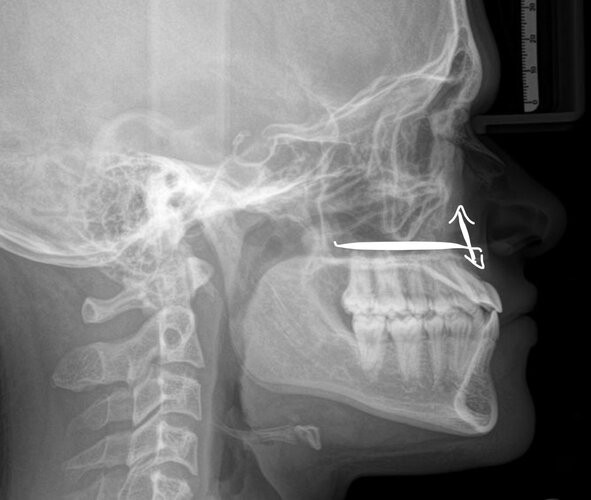

Current bite shown in the RX i know for sure my upper teeth need to go back by a lot to allow good movements thanks to being a camouflaged class 3

Current bite shown in the RX i know for sure my upper teeth need to go back by a lot to allow good movements thanks to being a camouflaged class 3